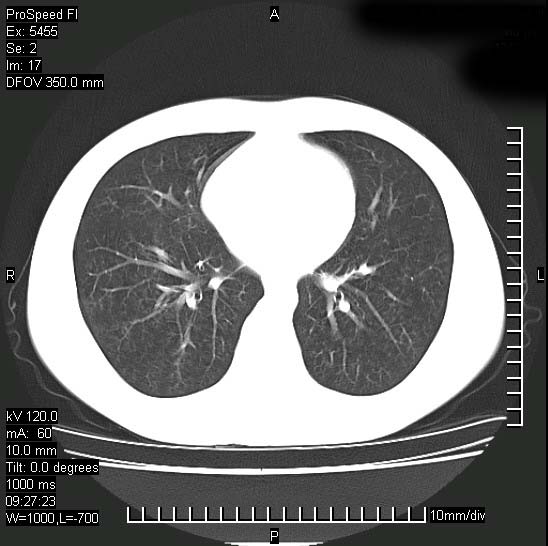

以下是引用zjzjr在2008-12-3 20:50:00的发言:[br]考虑泛细支气管肺炎,建议进一步检查除外肺出血性疾病如含铁血黄素沉着症、肺肾综合征等。

以下是引用zjzjr在2008-12-3 20:50:00的发言:[br]考虑泛细支气管肺炎,建议进一步检查除外肺出血性疾病如含铁血黄素沉着症、肺肾综合征等。

以下是引用光线在2008-12-3 20:19:00的发言:[br]双肺间质性改变。